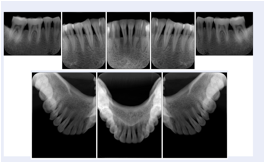

Intra-oral radiography typically involves acquisition of multiple images of various parts of the dentition. Many digital radiographic systems offer customized templates that are used for displaying the images in a study on the screen. These templates may also be referred to as mounts or view sets. The Structured Display Object represents a standard method of encoding and exchanging the layout and intended display of Structured Displays. A structured display object created in this manner could be stored with a study and exchanged with images to allow for complete reproduction of the original exam.

2. A patient requests cosmetic surgery to enhance their facial appearance. The case requires consultation between an orthodontist in New York and an oral surgeon in California. The cephalometric series of 2D projections constructed from a volumetric CT data set that is used for the discussion is arranged by a Structured Display for transfer between the two practitioners.

Cephalometric Series Structured Display

Figure OO-2. Cephalometric Series Structured Display

3. A dental provider wishes to capture a series of DICOM IO images for the patient’s dentition. The tooth morphology, teeth are divided into molars, premolars, canines and incisors, and a number of images for each jaw. The anatomic information was captured utilizing the triplet of schema. This standard code sequence is based on ISO 3950-2010, Dentistry - Designation system for teeth and areas of the oral cavity.

Every IO image should have anatomic information either through the primary or modifier sequence.

In most standard cases, images are oriented in structured layouts. These structured displays are useful to be shared between providers for reference purposes.

Table OO.1.1-1 shows structured display standard templates, where Viewset ID is based on the Japanese Society for Oral and Maxillofacial Radiology (JSOMR) classification provided by JIRA (Japan Medical Imaging and Radiological Systems Industries Association, www.jira-net.or.jp). Expected or typical teeth to be imaged location, region and designation codes are based on ISO 3950-2010, Dentistry - Designation system for teeth and areas of the oral cavity. For all the hanging protocols listed in OO.1.1-1, the value to use for Hanging Protocol Creator (0072,0008) is "JSOMR" and the value to use for Hanging Protocol Name (0072,0002) does not include "JSOMR" (e.g., "DL-S001A", not "JSOMR DL-S001A").